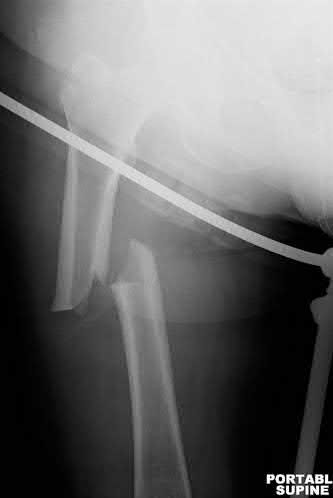

A 12-year-old obese boy presents with vague left thigh and knee pain. He is diagnosed with a Slipped Capital Femoral Epiphysis (SCFE) as seen in similar clinical scenarios.

During percutaneous in-situ fixation, unrecognized penetration of the guide wire into the hip joint occurs. What is the most likely specific complication resulting from this technical error?